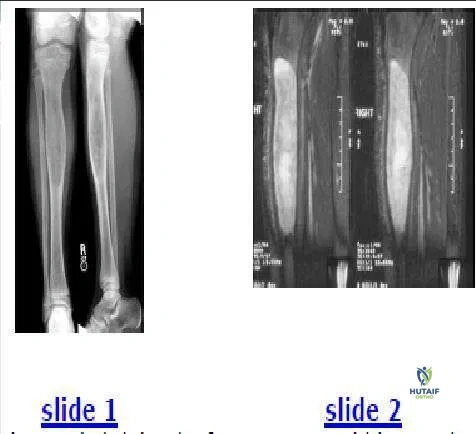

The radiograph (Slide 1) of an 11-year-old boy with significant leg pain is presented. No other abnormalities are found during the patientâ s history or physical examination. The most likely diagnosis is:

Fibrous dysplasia is chronically expansile with vague transition to normal bone and a â ground-glassâ appearance. These characteristics differentiate fibrous dysplasia from aneurysmal and unicameral bone cysts. Additionally, the lack of periosteal reaction differentiates fibrous dysplasia from malignancy or osteomyelitis. The patients magnetic resonance image (Slide 2) is also provided.